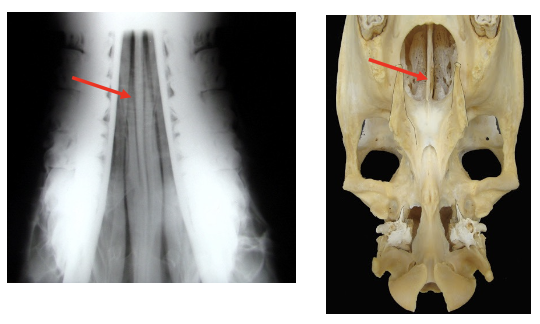

What is being indicated in these images?

Conchal bullae —> air filled but can become infected

then form dorsal & ventral conchae